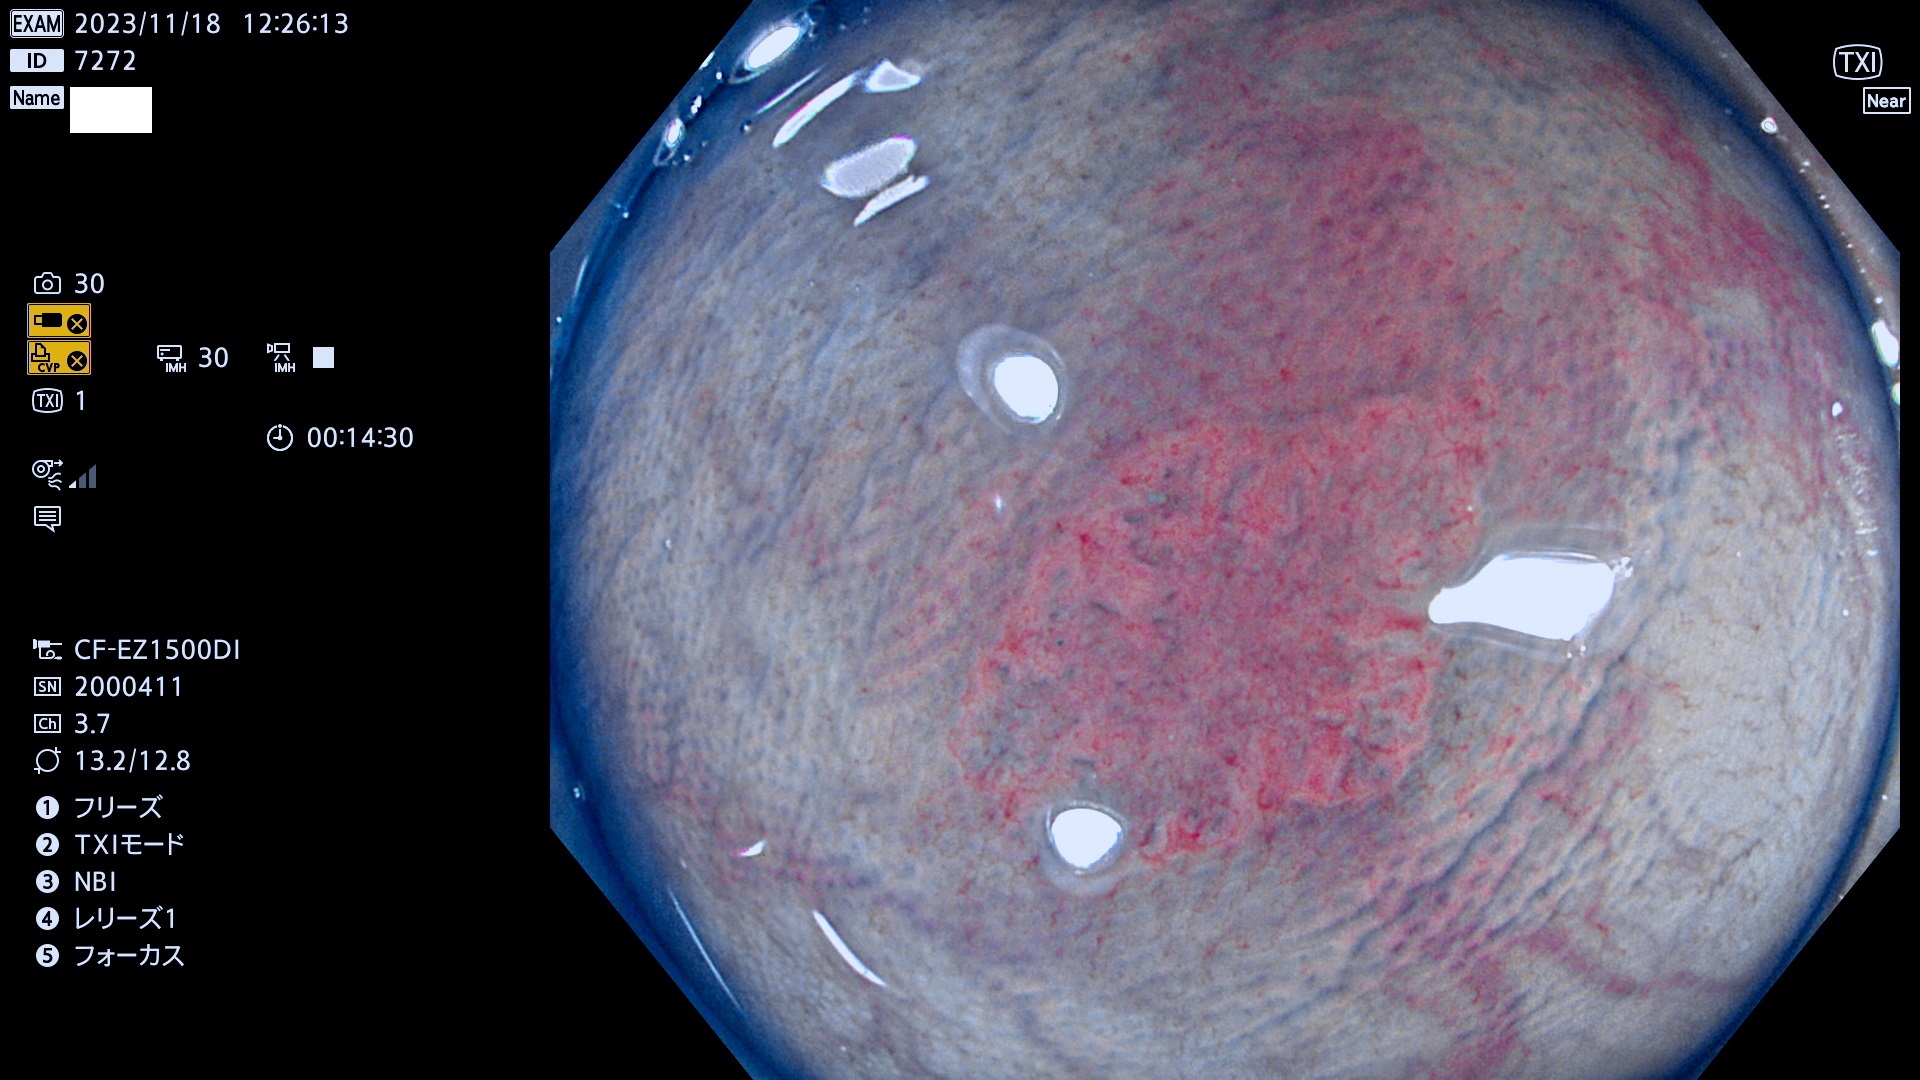

表面型腺腫(Flat Adenoma)の中で、完全に平坦な物をUb、陥凹している物をUcと呼びます。平坦隆起型(Ua)よりも、発見が難しく危険な病変です。このタイプは「内視鏡後・大腸癌の重要犯人」であり、この発見率は「腺腫発見率」よりも、重要な意味があります。

毎週の検査(木・金・土・日)に発見されたUb、Uc型・腺腫を、その週の日曜の夜にUPし1週間、提示します。

抽出の対象期間 2023年11月16日(木)〜11月20(日)の5日間(60件の検査)11件